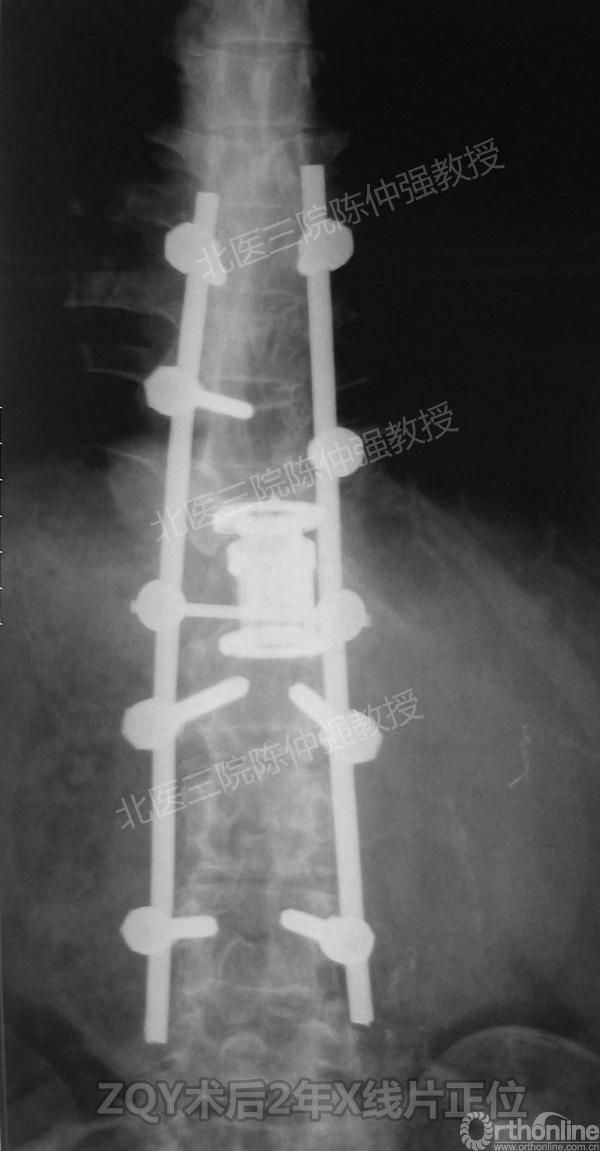

ZQY术后2年

患者女性17岁,胸腰椎陈旧结核性侧后凸畸形,局部呈“麻花状”扭转,无神经功能受损表现。2005年,陈仲强教授带领团队实施后路+侧前方联合入路脊柱节段切除、双轴旋转矫形术。术后患者外观显著改善,神经功能正常。术后随访证实患者截骨矫形节段骨性融合良好,矫形效果持续良好。